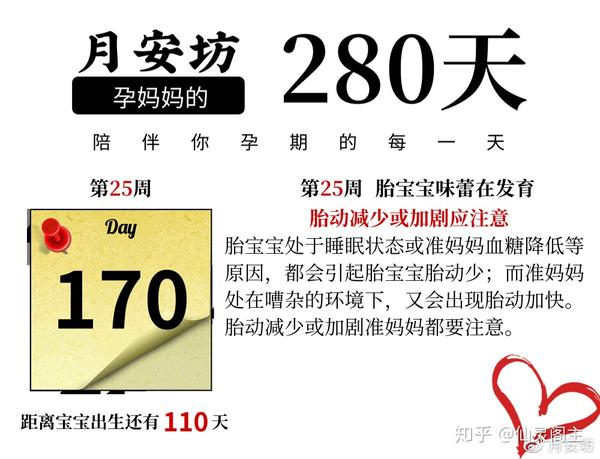

孕妈妈的280天 第25周 胎动减少或加剧 准妈妈都要注意 知乎

孕妈妈的280天 第25周 胎动减少或加剧 准妈妈都要注意 知乎

孕妈妈的280天 第25周 胎动减少或加剧 准妈妈都要注意 知乎